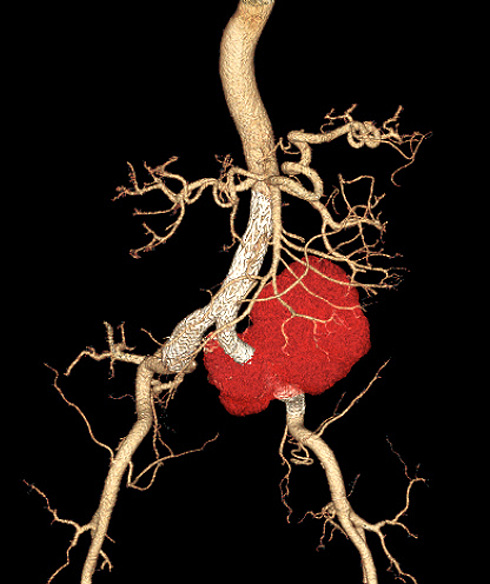

Aneurisma de ilíaca roto tratado com endoprótese